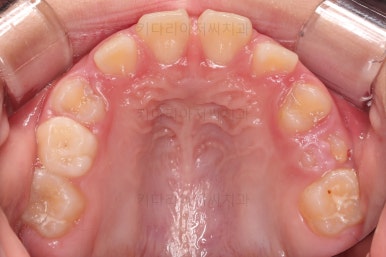

초진 시 입안의 모습입니다.

아래쪽 치열이 전반적으로 윗니보다 앞쪽에 위치한 전형적인 앵글씨 3급 부정교합인데요.

어금니에서부터 앞니까지 아랫니가 윗니보다 앞쪽에 위치하네요.

특히 앞니는 아랫니가 윗니보다 나와있는 "반대교합" 상태였고요.

또한 위아래로 겹침이 없고 떠있는 "개방교합" 상태였어요.

즉, 앵글씨 3급 부정교합 - 반대교합 - 개방교합 등 굉장히 복합적인 교합의 문제를 가진 환자였습니다.